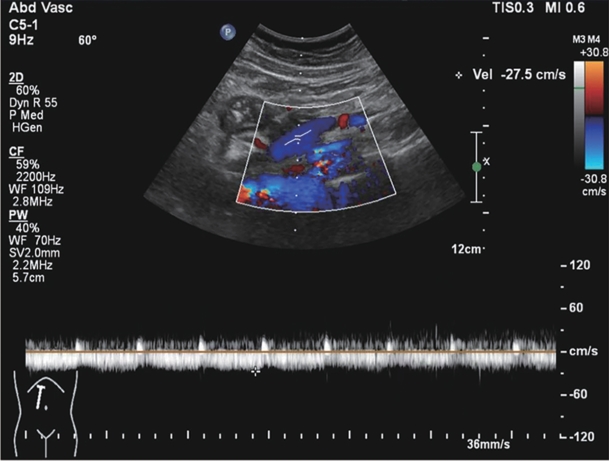

Large spontaneous splenorenal shunt embolization combined with anticoagulant therapy in treatment of portal vein thrombosis: A case report

Ju HUANG, Xiaoze WANG, Xuefeng LUO, Li YANG

2025, 41(8): 1639-1642. DOI: 10.12449/JCH250825

Abstract(513) HTML (178) PDF (3328KB)(71)

Abstract:

Portal vein thrombosis (PVT) is a common and severe complication in patients with liver cirrhosis, and alterations in portal hemodynamics are closely associated with the development of PVT. The presence of large spontaneous splenorenal shunt (SSRS) may lead to reductions in portal vein perfusion and blood flow velocity, which may compromise the anticoagulant effect on PVT. This article reports the treatment strategies of SSRS embolization combined with anticoagulant therapy that help to achieve complete recanalization of the portal vein; however, high-quality clinical studies are still needed to further validate and support the effectiveness of this strategy.